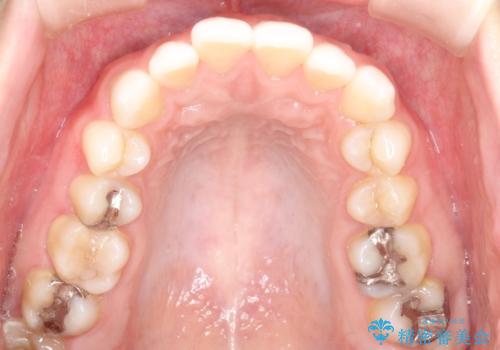

- 上下の前歯のがたつきを主訴に来院されました。

目立たない装置がご希望で、インザラインによるマウスピース矯正にて治療を行うこととなりました。

使用時間を守っていただけたので、スムーズに治療を終わることができました。